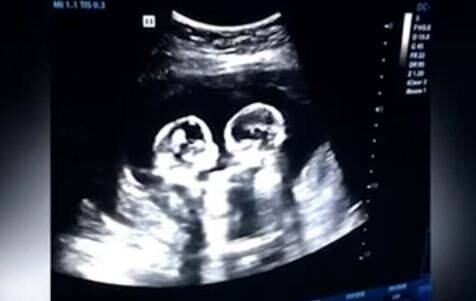

Al momento de nacer, Cherry y Strawberry fueron nombradas las pequeñas. Esto en alusión a los momentos que ofrecieron durante la gestación.

Las niñas fueron gemelas monoamnióticos monocoriales, lo cual significa que fue un embarazo de alto riesgo. El peligro más grande al que se enfrentaban estas pequeñas es que los cordones umbilicales se enredarán. Sin embargo, afortunadamente el 8 de abril a las 32 semanas a través de una cesárea nacieron completamente sanas.